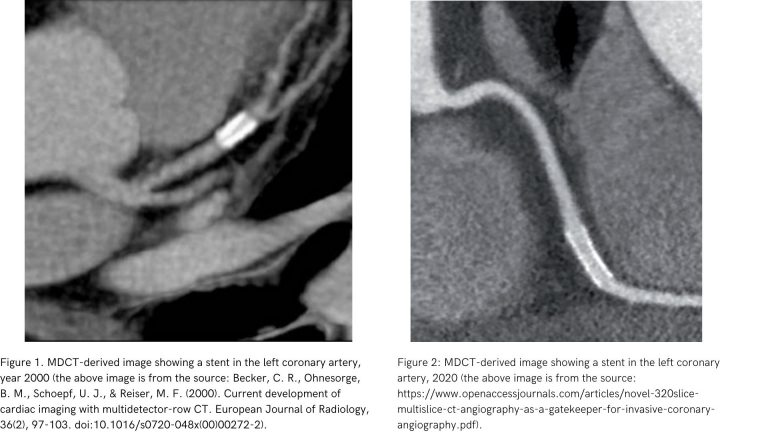

It should be noted, that the first multidetector computed tomography (MDCT) scanners were introduced in the early 1990s.[1]. Close to the emergence of the DICOM 3.0 standard, still used. Let us emphasize, that the past 20 years have been a time of intense development of this medical imaging modality.

Below there are the examples of coronary artery images obtained with MDCT in 2000 and 2020, respectively: